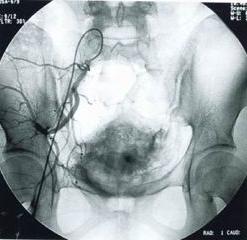

多數病人的症狀出現在某次分娩或流產後。臨床疑為盆腔靜脈瘀血症,可行盆腔靜脈造影協助診斷。輕症患者多不需要藥物治療。可針對其有關病因,給予衛生指導,如是中午、晚上休息時,採用側俯臥位,糾正便秘,節制房事,適當體育鍛鍊以增進盆腔肌張力及改善盆腔血循環。